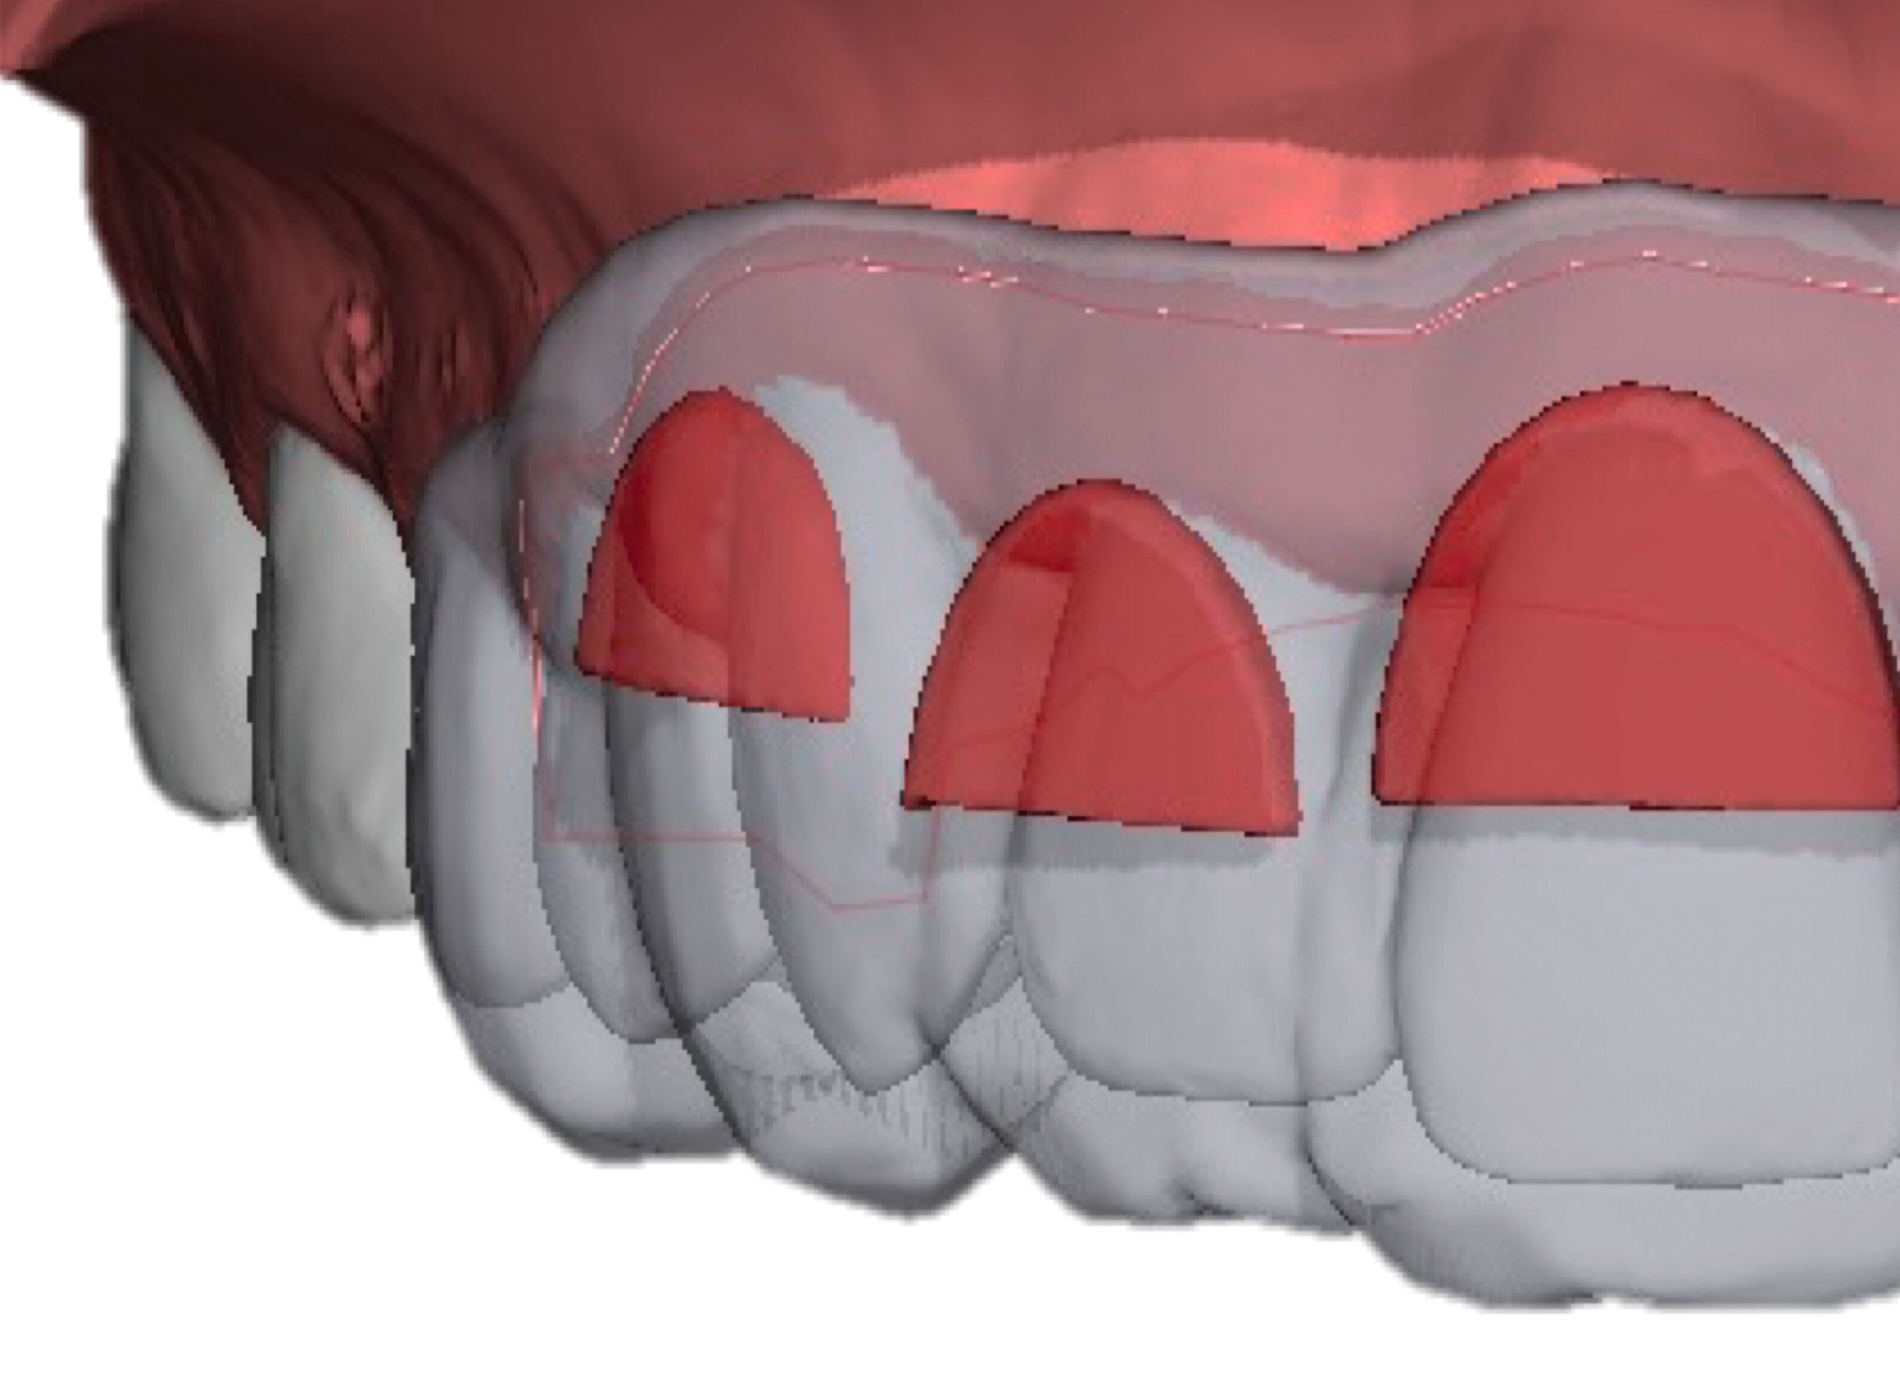

Weitere Beispiele beinhalten hochkomplexe Behandlungsfälle multipler Zahnanlagen. Während die Extraktionsentscheidung und Absprache mit dem/der chirurgisch tätigen Kollegen/in allein auf Basis der Bildgebung oft limitiert ist, erleichtern 3-D-gedruckte Modelle des segmentierten DVTs sowohl die Entscheidung als auch die Absprache und ermöglichen darüber hinaus eine genauere Planung des chirurgischen Vorgehens (Abbildung 6c). Gleiches betrifft parodontalchirurgische Eingriffe, in denen sogenannte „Cutting guides“ eine zuvor digital geplante Gingivektomie ermöglichen (Abbildung 6d). Im Bereich der Freilegung verlagerter Zähne können Schablonen dem/die chirurgisch tätigen Kollegen/in sowohl die Freilegung des Zahnes (Abbildung 6e) als auch die Anbringung eines Attachments (Abbildung 6f) erleichtern und dabei die kieferorthopädisch gewünschte Attachmentposition passgenau übertragen.